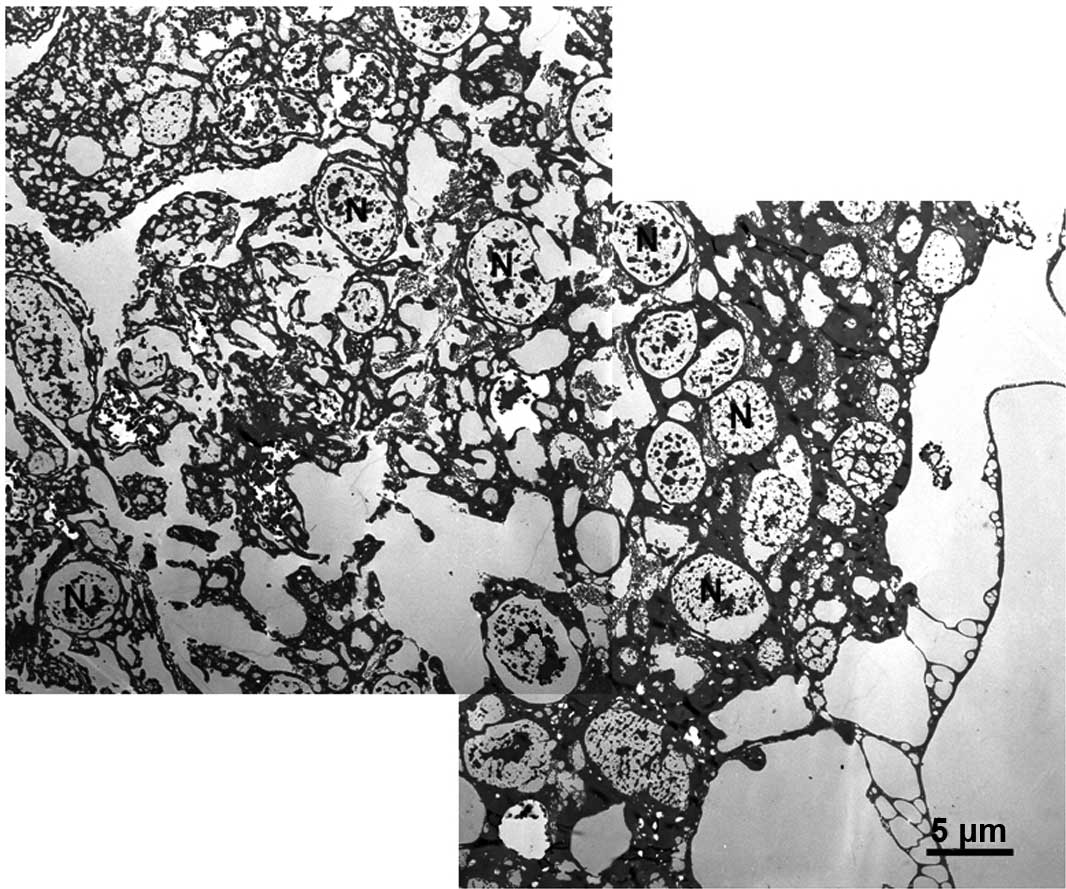

Figure 2

Electron microscopical analysis of the treatment of a giant cell tumour (GCT) with 6% phenol for 1 min, ∼10 μm along from the zone shown in Fig. 1. As already evident in the left panel of Fig. 1, the cellular structure is relatively well maintained.